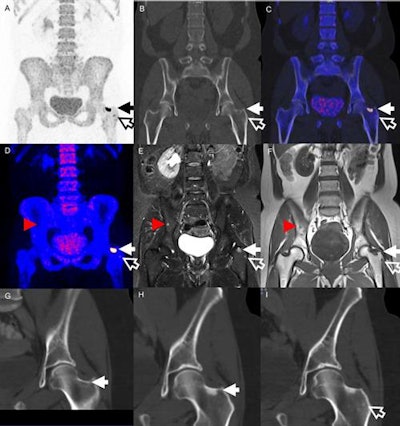

Images are from a 51-year-old woman treated for locally advanced breast cancer. Two lesions in the left hip were identified on both PET (A-C) and MRI (D-F) (solid and hollow arrows). The larger lesion could be found retrospectively on a diagnostic CT (G) one month prior to PET. CT two months after treatment (H) shows a sclerotic transformation of the lesion. The smaller lesion (I) has also turned sclerotic. MRI showed an additional lesion in the pelvic bone (red arrowheads) not identified on PET. Images courtesy of JNM.

Images are from a 51-year-old woman treated for locally advanced breast cancer. Two lesions in the left hip were identified on both PET (A-C) and MRI (D-F) (solid and hollow arrows). The larger lesion could be found retrospectively on a diagnostic CT (G) one month prior to PET. CT two months after treatment (H) shows a sclerotic transformation of the lesion. The smaller lesion (I) has also turned sclerotic. MRI showed an additional lesion in the pelvic bone (red arrowheads) not identified on PET. Images courtesy of JNM.There are also advocates for NaF-PET/CT imaging for bone metastases, given the hybrid modality's efficacy in oncologic applications and shorter uptake time from NaF administration to scanning, compared with planar bone scintigraphy. Whole-body MRI has also gained attention, with its ability to detect early bone marrow lesions compared to CT, and combining it with NaF-PET could further improve bone metastases evaluation.